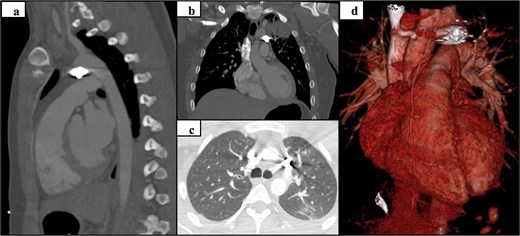

Trauma workup imaging began with a chest X-ray (CXR), triggering a chest CT given the bullet’s location in the mediastinum. With the bullet near the great vessels, a transthoracic echocardiography (TTE) and a CT using a cardiac gated/dissection protocol were obtained. The visualization of vasculature and normal anatomy was limited by metallic artifact from the foreign body (Fig. 1). The chest CT demonstrated the largest bullet fragment located in the region of the aortopulmonary window, with no measurable distance between the bullet fragment and inferomedial margin of the aortic arch (Fig. 2). Less than 2 mm of separation was visualized between the bullet and the superior aspect of the left main pulmonary artery (Fig. 2). There was no contrast extravasation from the vasculature to suggest active bleeding, and there was no obvious mediastinal fluid collection / hematoma. TTE also visualized the aortic arch and showed no clear injury with laminar flow across the aorta. His initial CXR demonstrated a normal cardio-mediastinal silhouette (Fig. 1a). A small pneumothorax was seen with 2 mm pleural separation but repeat CXR did not indicate expansion, so chest tube placement was deferred (Fig. 1a and b). Upper extremity imaging suggested soft tissue laceration and bullet trajectory without arterial damage.

Preoperative CT and 3D reconstruction: sagittal (a), coronal (b), axial (c), and 3D reconstruction (d).